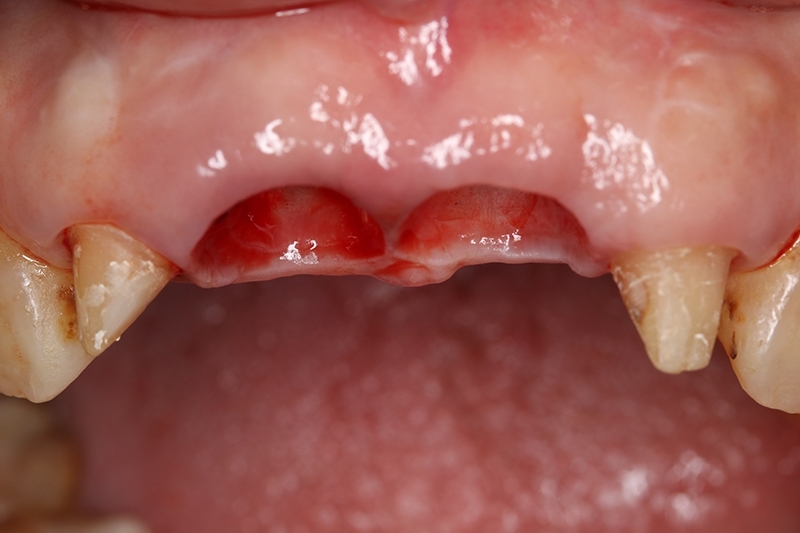

可見植體移除後骨缺損範圍大

取出的舊有one piece植體,舊式植體。

初步等待2個月軟組織癒合,再來進行垂直脊水平骨牙脊增寬術,使用不可吸收再生膜Cytoplast 及迷你骨釘 Tack固定放置的人工骨粉。